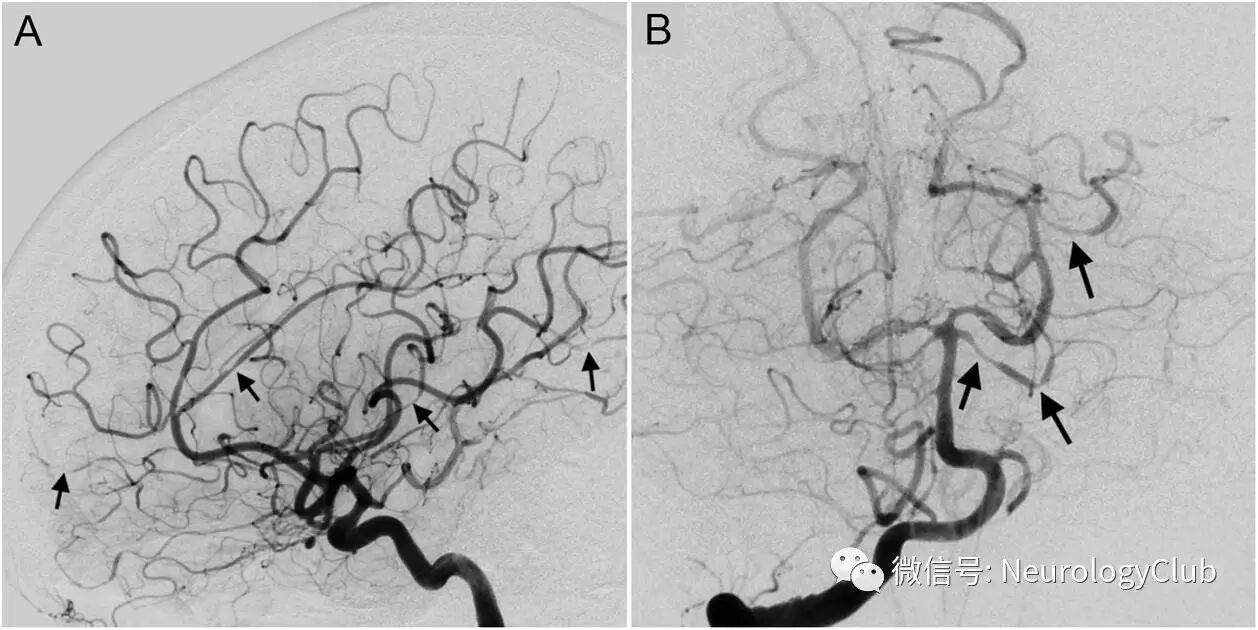

(图2:A:右侧颈内动脉血管造影;B:右侧椎动脉血管造影;多处血管支配可见多灶性节段性血管收缩[箭])

头颅CT可见左侧额叶较小范围的凸面蛛网膜下腔出血(cSAH)(图1)。CT血管造影无殊(未放图)。MRI可见双侧顶枕叶T2/FLAIR高信号,可符合可逆性后部脑病综合征(PRES)(图1)。脑血管造影提示多灶短节段狭窄,主要见于左侧大脑前和大脑中动脉的远端皮质支(图1)以及左侧小脑上动脉近端和多处其他血管支配区(图2)。未见动脉瘤或血管畸形。